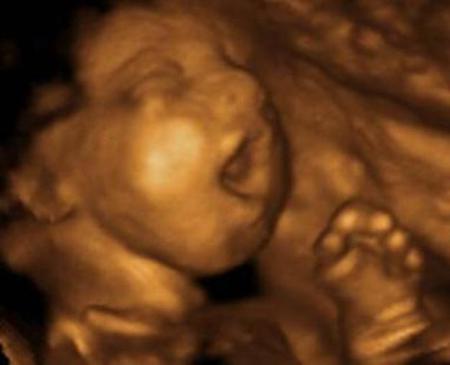

–Ha cesado el dolor. Pero siento que sigo siendo. Soy, existo. Sé perfectamente cuándo fui concebido. En ese instante, el eco distante de una gran explosión se repitió en mi, a partir de ese momento empecé a ser. Ahora solo queda mi corazón allá, que se niega a dejar de latir en aquel vientre.

–Para ayudarte en tu trance te explicaré todo. Aunque debo confesarte que me preocupa que todavía lata tu corazón. Ya deberías haber hecho tu tránsito, porque todos tus trozos están en la cubeta. Desde aquí veo al médico retirar los instrumentos del lado de la que iba a ser tu madre, que se ve desfallecida todavía con las piernas abiertas, y bastante sangre. Sin duda, algo extraño ha sucedido. Supongo que más adelante bote tu corazón. Lo que no me explico es cómo sigue palpitando. . . Te han abortado utilizando un método muy antiguo y común, que es el raspado. Dilatan el útero e introducen por la vagina instrumentos afilados para ir raspándolo. Si todavía eres embrión, sales como un coágulo grande. Si eres feto, como fue tu caso, entonces te van arrancando a pedazos. También está la succión que se realiza por medio de un tubo plástico con una aspiradora en la punta, y te van aspirando, como basura. De nada le sirve al feto moverse, huir, tratando de esconderse del vacuum cleaner por todo el vientre. Siempre te traga. Hay otros métodos, claro, como las pastillas que provocan el aborto rápido, o inyectar el pecho del bebe para parar su corazón y después tratar de inducir el parto. Si esto falla, dilatan más, lo agarran con unas tenazas y empiezan a darle vueltas. La cabeza quedará atrapada en la parte baja del útero. Le introducen entonces un tubito por la cabeza para sacarle el líquido y reducírsela, así sale fácil. Por supuesto, hay millones de mujeres que tratan de abortar sin recurrir al médico porque no tienen dinero, porque es ilegal o por ignorancia. Toman todo tipo de brebajes, se duchan con cuanto líquido te puedas imaginar, desde amoniaco hasta detergentes de lavar la ropa. Si no, recurren a algo que creen más seguro: introducirse instrumentos cortantes para sacarse el embrión o feto: se meten agujas de tejer, alambres de percheros, objetos de vidrio, muchas veces hasta se perforan ellas mismas el útero. Otras veces se tiran de mesas, de sillas, dan brincos. Es preferible dejarlos morir en la cubeta, como tantas veces sucede cuando el muchacho sale vivo.

–En su olvido, ¿olvidan también que el alma no nace cuando nacen ellos, sino mucho antes? ¿Qué el misterio se aloja en el embrión desde que este empieza a flotar en el líquido amniótico?